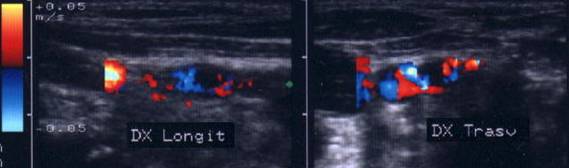

Acelasi caz. La doppler color - vascularizatie interna, mai evidenta in powerdoppler.